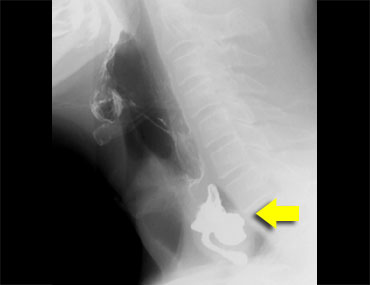

TRÁI: túi thừa nhỏ. GIỮA và PHẢI: túi thừa Zenker thực sự do đóng sớm của cơ nhẫn hầu (mũi tên vàng)

Túi thừa Zenker

Túi thừa Zenker luôn là hậu quả của rối loạn chức năng cơ nhẫn hầu.

Đóng sớm của cơ nhẫn hầu dẫn đến tăng áp lực trong hạ hầu, ngay phía trên cơ nhẫn hầu, khi sóng áp lực của các cơ khít hầu đẩy bolus xuống dưới.

Áp lực tăng này có thể gây phồng ra tại điểm yếu trên thành hầu sau (khe hở Killian).

Ban đầu sẽ tạo thành một túi nhỏ, theo thời gian có thể phát triển và hình thành túi thừa Zenker thực sự (Hình).